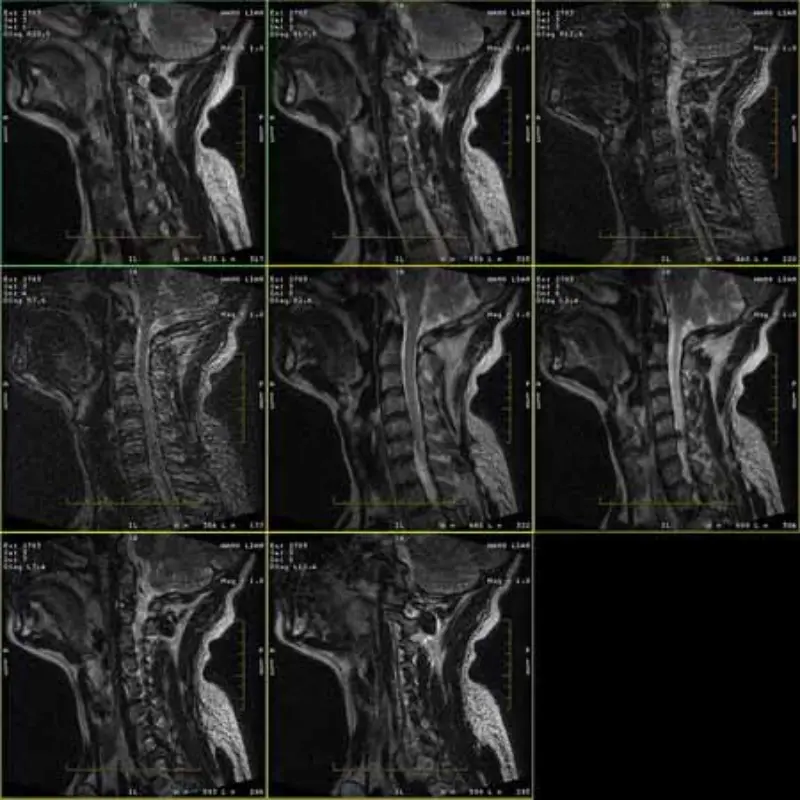

Ang mga larawan ng mga protocol ng FRFSE at GRE ay may ghost at kung minsan ay lumalabas sa isang serye ang mababang SNR na imahe. Ngunit ang mga imahe ng SE protocol ay normal.

Pakitingnan ang mga attach na larawan.